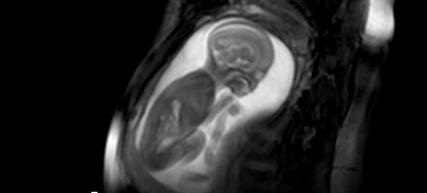

Από τα πρώτα στάδια της ανάπτυξης, όπως φαίνεται στο βίντεο, τα καρδιακά κύτταρα ενός έμβρυο ποντικού αρχίζουν να οργανώνονται αυθόρμητα σε σχήμα που μοιάζει με αυτό καρδιάς